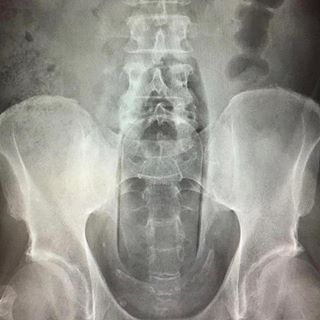

据统计,在急诊室中,男性“失物招领”的情况是女性的40倍,大部分失物是在肠道中被发现的,而且花样繁多……